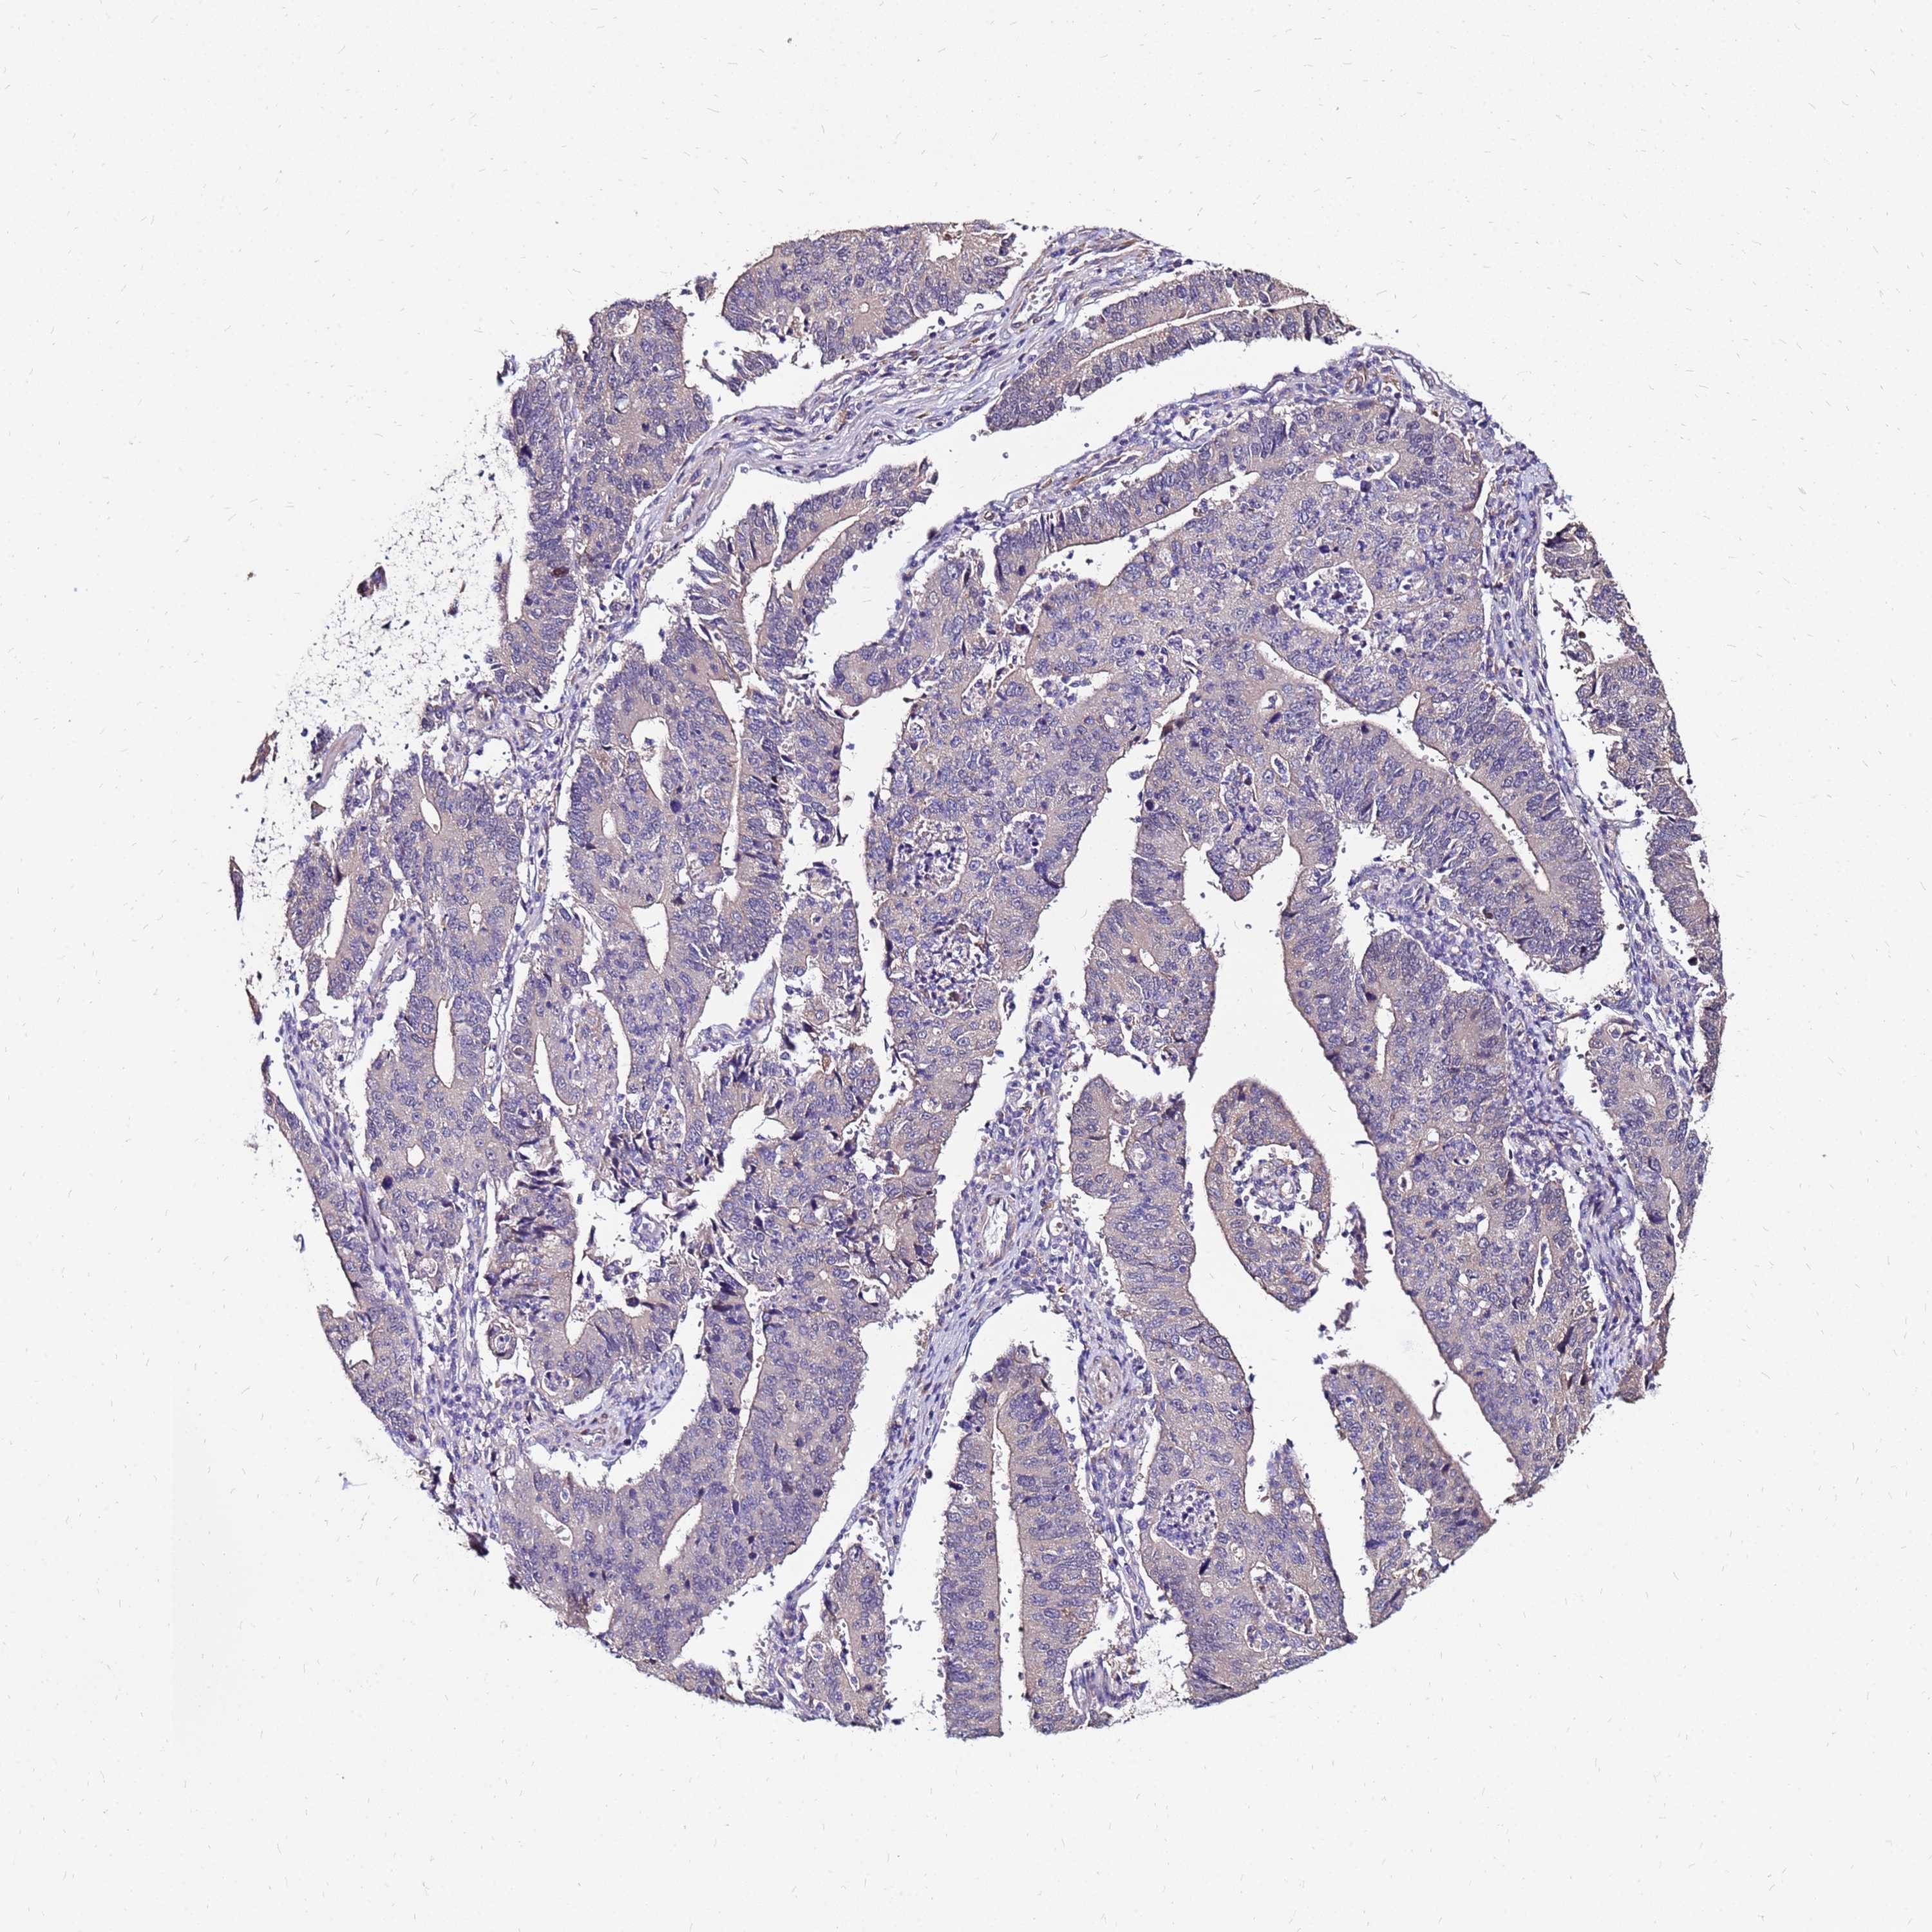

STOMACH CANCER - Protein expressioni

A mouse-over function shows sample information and annotation data. Click on an image to view it in a full screen mode. Samples can be filtered based on level of antibody staining by selecting one or several of the following categories: high, medium, low and not detected. The assay and annotation is described here.

Antibody stainingi

Antibody staining in the annotated cell types in the current human tissue is reported as not detected, low, medium, or high, based on conventional immunohistochemistry profiling in selected tissues. This score is based on the combination of the staining intensity and fraction of stained cells.

Each image is clickable and will lead to virtual microscopy that enables deeper exploration of all samples and also displays staining intensity scores, fraction scores and subcellular localization as well as patient and tissue information for each sample.

Antibody HPA044188

Antibody HPA045619

Antibody HPA045699

Staining

High

Medium

Low

Not detected

Intensity

Strong

Moderate

Weak

Negative

Quantity

>75%

75%-25%

<25%

None

Location

Nuclear

Cytoplasmic/membranous

Cytoplasmic/membranous,nuclear

Adenocarcinoma, NOS